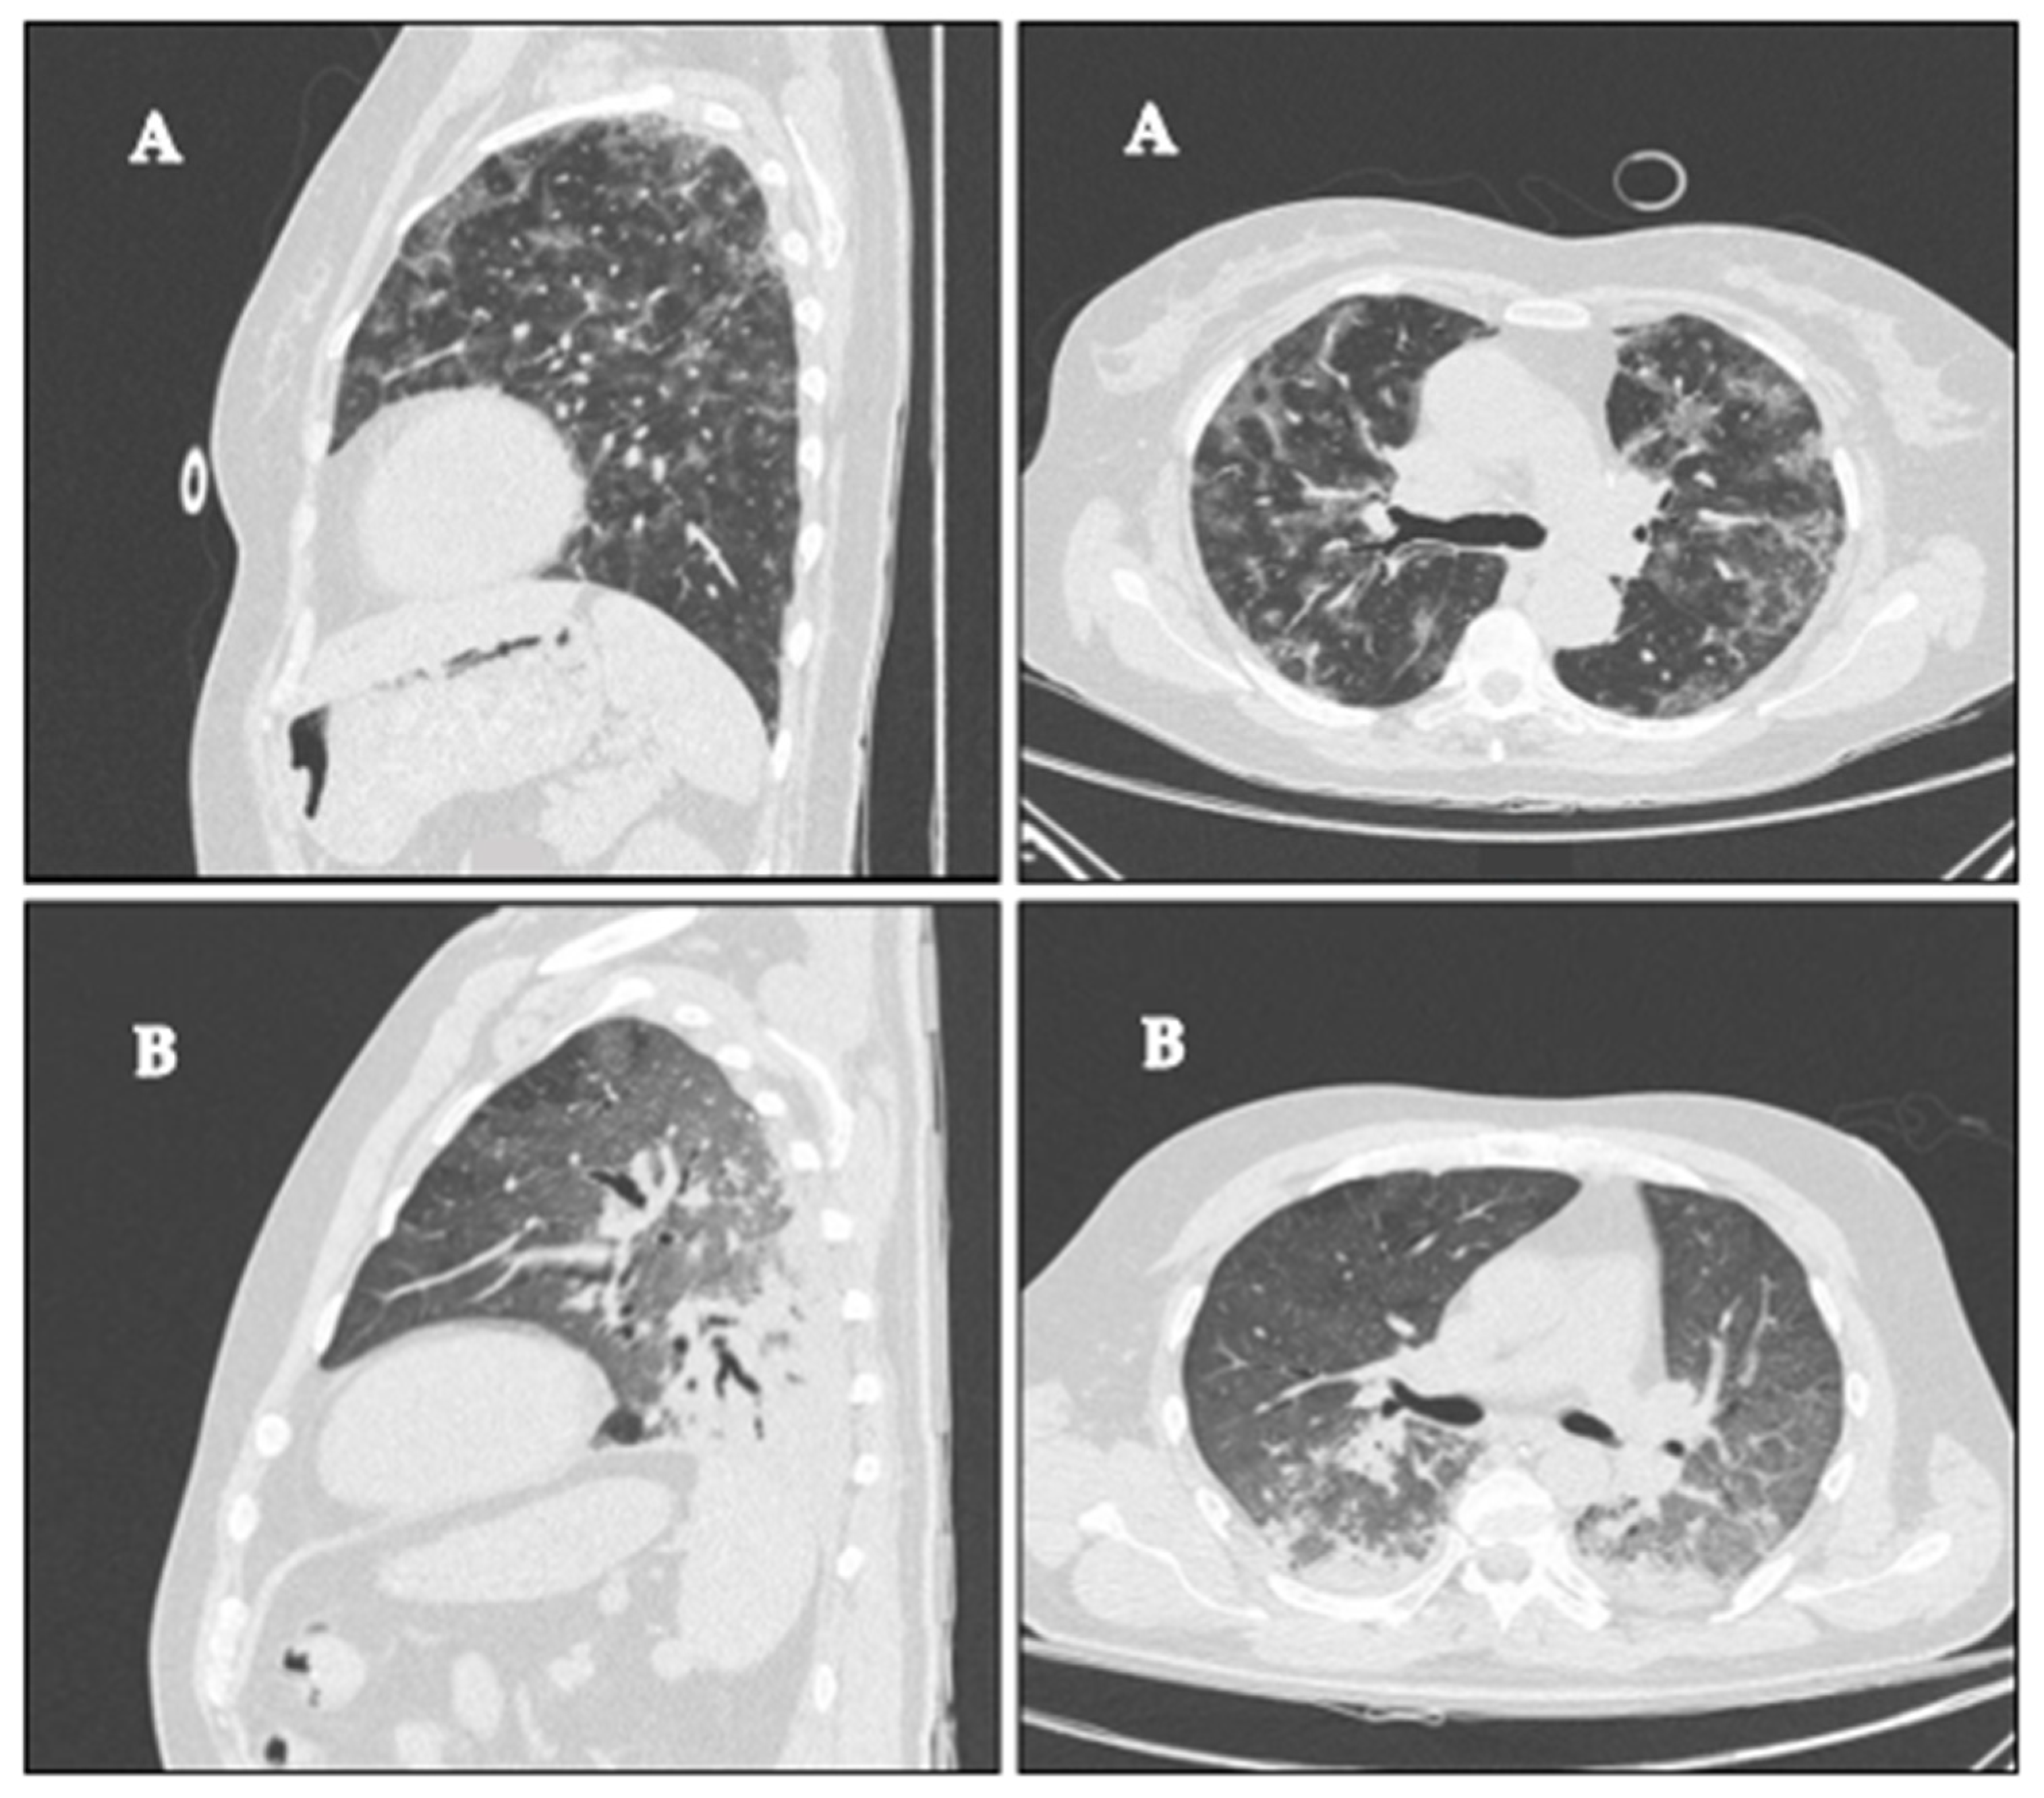

3.1. Chest CT Parenchymal Abnormalities

3.2. Response to Prone Position and Correlation with Imaging